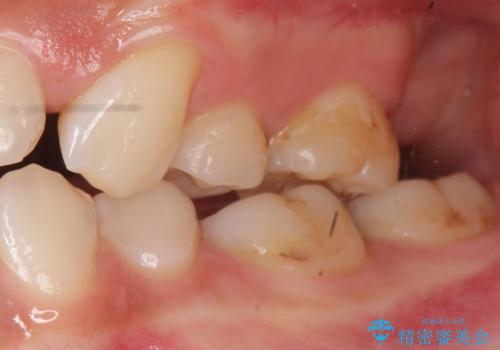

フロスを通すと臭い 歯と歯の間の虫歯 セラミックインレー 30代女性

- 歯と歯の間の虫歯治療を希望された患者様です。

フロスを通すと臭いのが気になるとの事でした。

精査したところ、左上の奥歯の間(左上56間)にう蝕を認めました。

う蝕を丁寧に除去したのち、セラミックインレーによる修復を行いました。